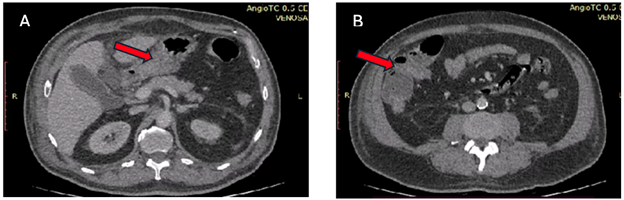

En sospecha de infarto mesentérico se solicita angiotomografía de abdomen fase arterial y venosa, evidenciándose, con un páncreas con adecuado tamaño con rebordes, realce homogéneo al medio del contraste, vesícula biliar con paredes edematizadas, arteria aorta abdominal y vena cava inferior de calibre conservado, con adecuada opacificación al medio del contraste, placas de ateromas cálcicas en la aorta e iliacas, cambios inflamatorios de la grasa perirrenal bilateral, escaso liquido libre, distorsión de la grasa a nivel de epigastrio masa grasa inflamada con pseudo capsula, que mide 80 x 70 mm, este último compatible con el diagnostico de infarto omental en epigastrio, ver Figura 1 y Figura 2.

Figura 1. Tomografías de abdomen con contraste en fase venosa, A) corte axial donde se observan distorsiones de la grasa a nivel de epigastrio, B) masa grasa inflamada con pseudocapsula, mide 80x 75 mm característico infarto omental en epigastrio.